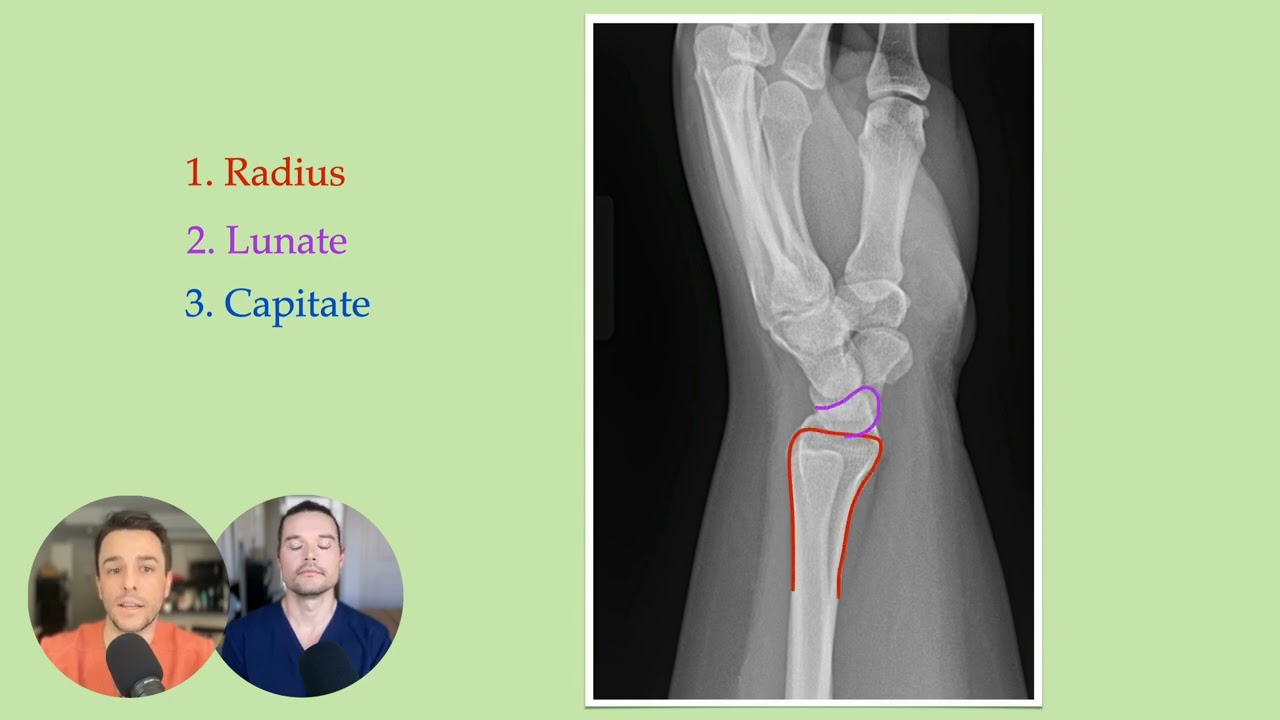

Lunate vs Perilunate Dislocation - ALL YOU NEED TO KNOW

Not only do you need to be able to catch this diagnoses in the department, you need to be able to clench this diagnosis on the boards! After you finish this video, you'll never confuse these again!!